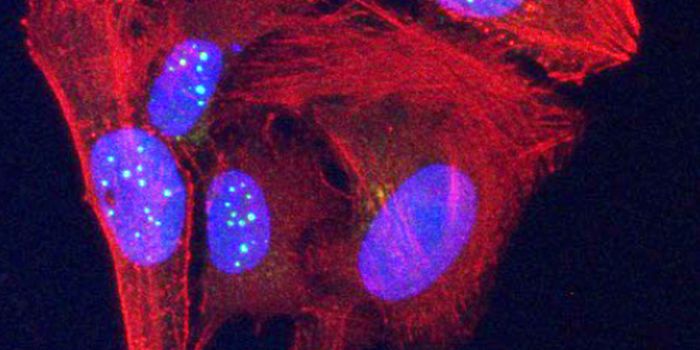

FEB 21, 2023Cell & Molecular BiologyThe Griffith Lab at UNC discovered telomeric protein & potential biomarker VR (green), shown in the nuclei (blue) of hum ...